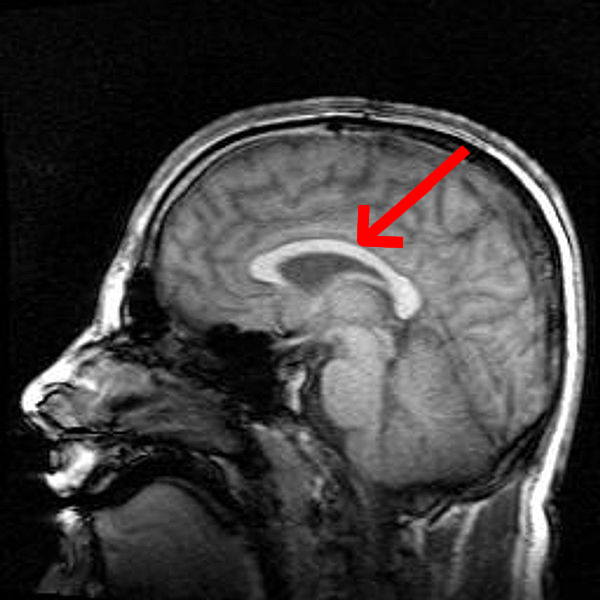

Het verwerken van taalklanken door mensen en zangvogels